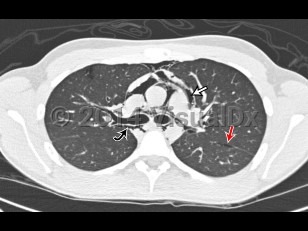

Pneumomediastinum is the presence of air in the mediastinum. It is caused by injury, most often esophageal or intestinal perforation. It can rarely occur spontaneously in children with acute asthma attacks (severe cough) and is also seen as a result of aggressive bag-valve mask ventilation during resuscitation and intubation as well as a result of barotrauma in intubated patients.